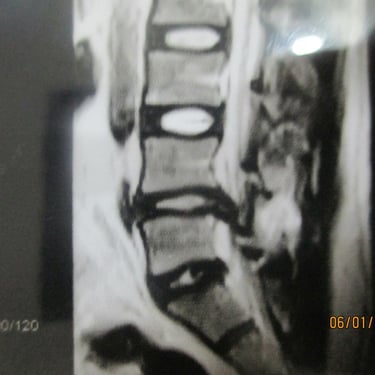

C5-C6 & C6-C7 disc herniation Before(desktop: left) and After the Discogel injection(desktop: right)